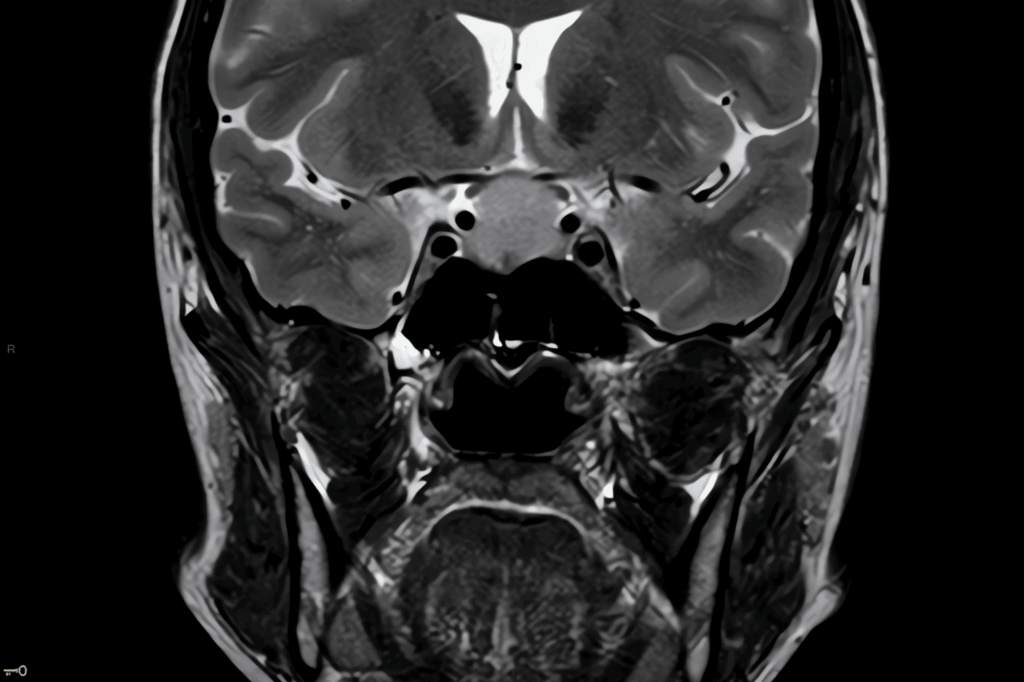

irm hypophysaire à Lyon - réduit

L’IRM de l’hypophyse est réalisée pour détecter la présence éventuelle d’une tumeur bénigne à ce niveau. Cet examen est recommandé pour les patients qui présentent des problèmes hormonaux ou un syndrome de Cushing. Avant de commencer l’examen, veuillez retirer tous vos vêtements, bijoux et objets métalliques et enfiler la blouse d’examen fournie. Si nécessaire, un cathéter sera installé pour l’injection de produits de contraste. Vous serez allongé et une sonnette d’alarme vous sera donnée pour communiquer avec le personnel pendant l’examen qui dure généralement environ une demi-heure. Il est important de rester le plus immobile possible pendant cette période. Il se peut que notre équipe vous demande de retenir votre respiration pendant quelques secondes en cours d’examen.